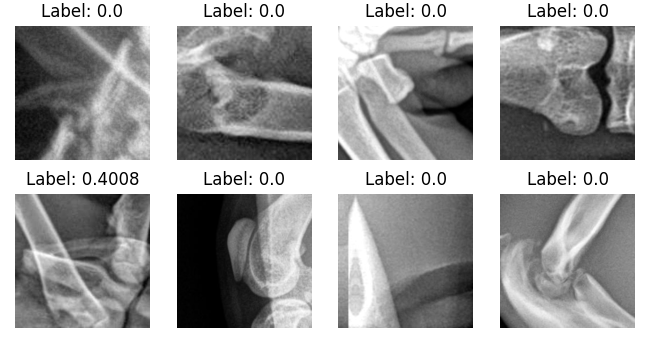

Increased interpretability of the results

To obtain a more holistic understanding of model performance, we use 6 major visual features identified during data analysis as a guide for understanding the model’s decision-making process. Figure 5 displays the performance of the clustering system on example-saliency crops with each one of the major visual features.

All of the saliency crops selected as representative of vertical lines were assigned by the KNN to cluster 2, and all the horizontal lines to cluster 5, along with most oblique lines. Interestingly, different views of medical devices appear to be clustered separately, with frontal views of the plate found in cluster 3 and crops containing the screws in cluster 0. The zoomed out crops, which mostly represent aberrant mistakes, are found in cluster 4. Finally, the crops without lines are mostly found in cluster 1.